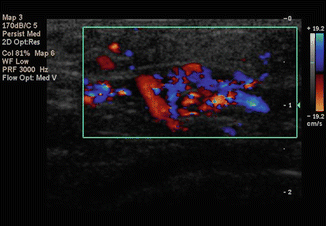

12.2.3.3 High-Frequency Ultrasound/Doppler

Ultrasound (US), especially with a high-resolution transducer, has been advocated as useful in examining small and superficial soft tissue masses that are suggestive of hemangiomas or vascular malformations. Vascular tumor ultrasound stands as one of the easier and more universally practiced noninvasive techniques [8] that give information about size, shape, depth, and, more importantly, vascularity [9]. In addition, US will help differentiate between a cystic and a solid lesion. Doppler US will give information about the presence or absence of flow and the degree of vascularization (Fig. 12.4). The Doppler characteristics of vascular malformations are helpful in differentiating low- from high-flow vascular malformations [10]. The sonographic depiction of abundant low-flow vascular channels can be a predictor of the potential success of percutaneous sclerosis. In addition, US can be used to guide needle placement during percutaneous sclerosis in a combination treatment approach (cryosurgery plus infiltration).

Fig. 12.4

Color Doppler analysis of the vascular mapping of a vascular malformation in the abdomen of a child